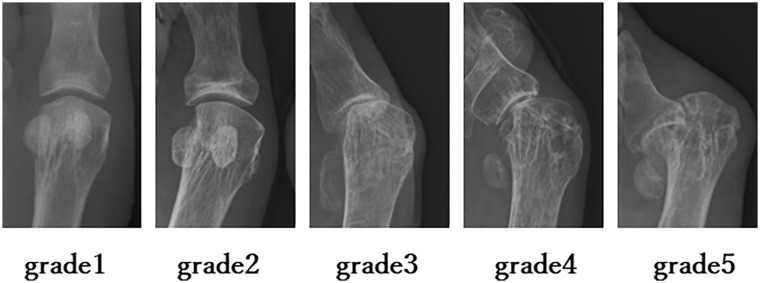

Methods: This single-center retrospective study at Kyushu University Hospital reviewed RA patients who underwent either first MTP joint arthrodesis or joint-preserving surgery for hallux valgus (HV) deformity between January 2008 and December 2022. A total of 103 feet (73 cases) were analyzed, with 75 feet (58 cases) showing radiographic bone destruction of Larsen grade 3 or higher. One foot underwent resection arthroplasty, so ultimately 74 feet in 57 cases were evaluated. Surgical procedures included joint-preserving biplane osteotomy or arthrodesis with crossed screws. Clinical outcomes were measured using the Japanese Society for Surgery of the Foot (JSSF) Hallux scale, whereas radiographic assessments included HV angle (HVA). Propensity score matching was used to minimize bias when comparing postoperative outcomes between the arthrodesis and joint-preserving surgery groups.